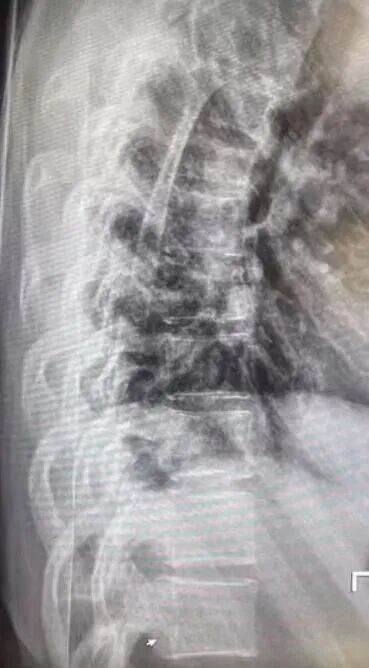

Mia紧急回应,晒出2024年航班事故的X光片和住院记录,称当时因湍流摔伤脊椎,同行者遇难,留下心理阴影,此次是PTSD被触发。